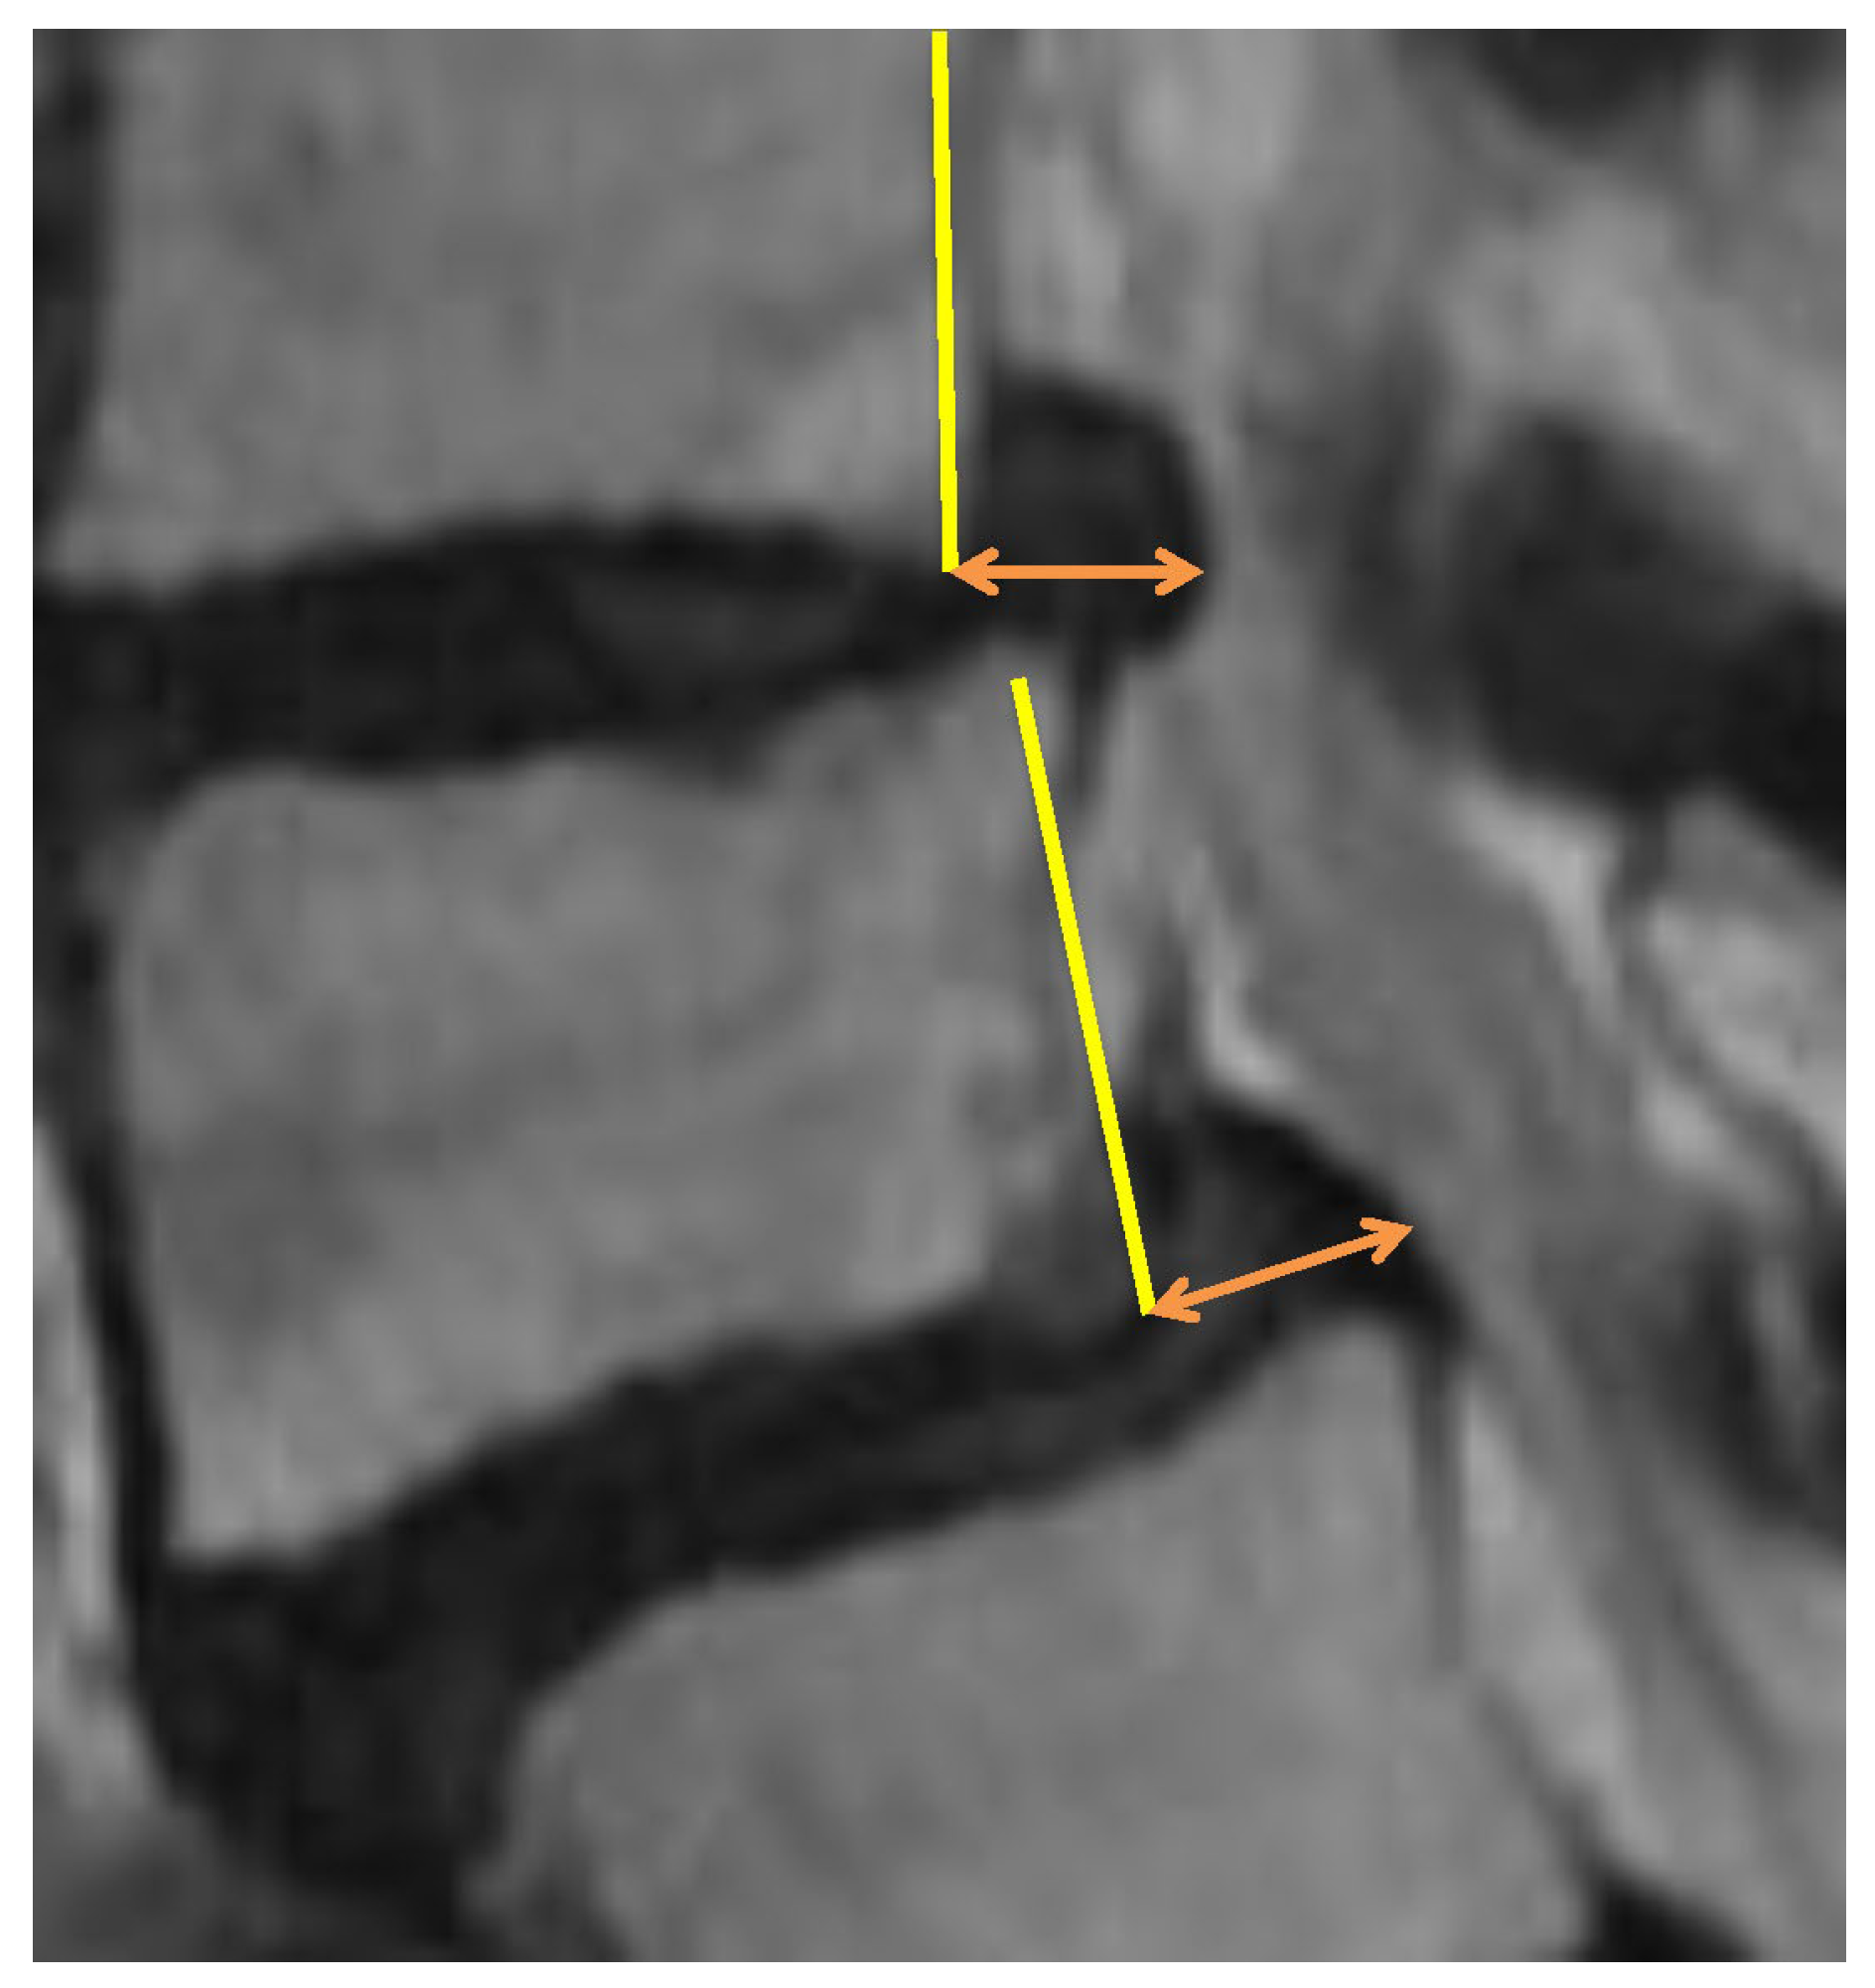

The measurement objects were the backward bulging length and the intervertebral height extension length. The definition for the backward bulging is the maximum posterior bulging length from the posterior surface of the vertebral body located forward at the level of the intervertebral disc (Figure 1).

Figure 1. Definition of the “backward bulging” is posterior bulging length (orange arrow) from the posterior surface of the vertebral body (yellow line) at the level of the intervertebral disc.